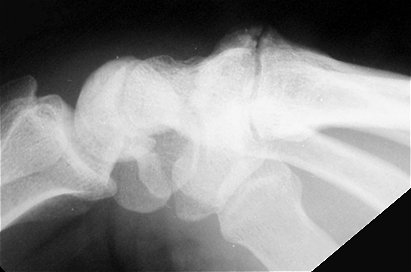

Metacarpal boss Xray view